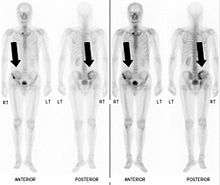

Bone Scintigraphy

Also known as a bone scan, bone scintigraphy involves the injection of a small amount of radioactive tracer into the bloodstream. This tracer decays and emits radioactive energy which can be detected by a special camera. The camera produces a black and white image where areas shown as dark black indicate bone damage of some kind. If there is a black spot in the lumbar vertebrae (e.g. L5) this indicates damage and potentially spondylolysis. If this test is positive, a CT scan is usually ordered to confirm spondylolysis.[12]

Computed Tomography

Commonly known as a CT Scan or CAT scan, this form of imaging is very similar to x-ray technology but produces many more images than an x-ray does. The multiple images produce cross-sectional views not possible with an x-ray. This allows a physician or radiologist to examine the images from many more angles than an x-ray allows. For this reason the CT scan is much more accurate in detecting spondylolysis than an x-ray. Bone scintigraphy combined with CT scan is considered the gold standard which means that it is best at detecting spondylolysis.[12][14]